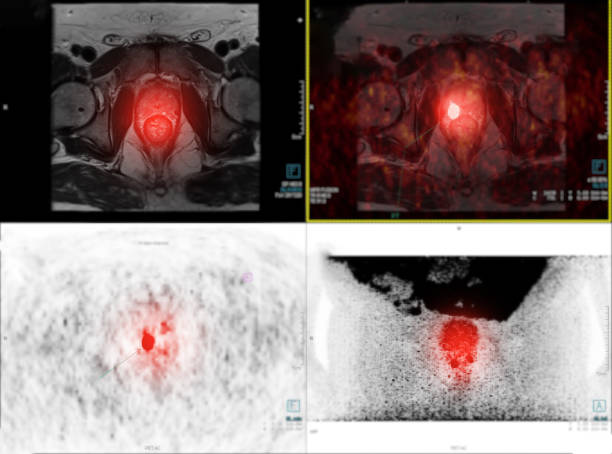

전립선암은 초기에는 증상이 나타나지 않고, 발견이 어려운 경우가 많습니다. 하지만 조기에 발견하면 완치가 가능하며, 그렇지 않은 경우에는 중등도 이상의 항암제 치료나 방사선 치료, 수술 등의 치료가 필요할 수 있습니다. 따라서, 전립선암 초기 증상을 인지하고 주기적인 건강검진을 받는 것이 중요합니다. 그래서 이번 시간에는 전립선암 초기증상에 대해 자세히 알아보겠습니다.

전립선암은 남성에서 가장 흔한 악성 종양 중 하나로, 전립선에서 발생하는 암입니다. 전립선은 남성의 생식기관 중 하나로, 회음부와 방광 사이에 위치하며, 요도 주위를 둘러싸고 있습니다. 전립선은 대부분의 경우 선천적으로 발생한 것은 아니며, 남성이 노화에 따라 서서히 성장하면서 발생하는 것으로 알려져 있습니다.